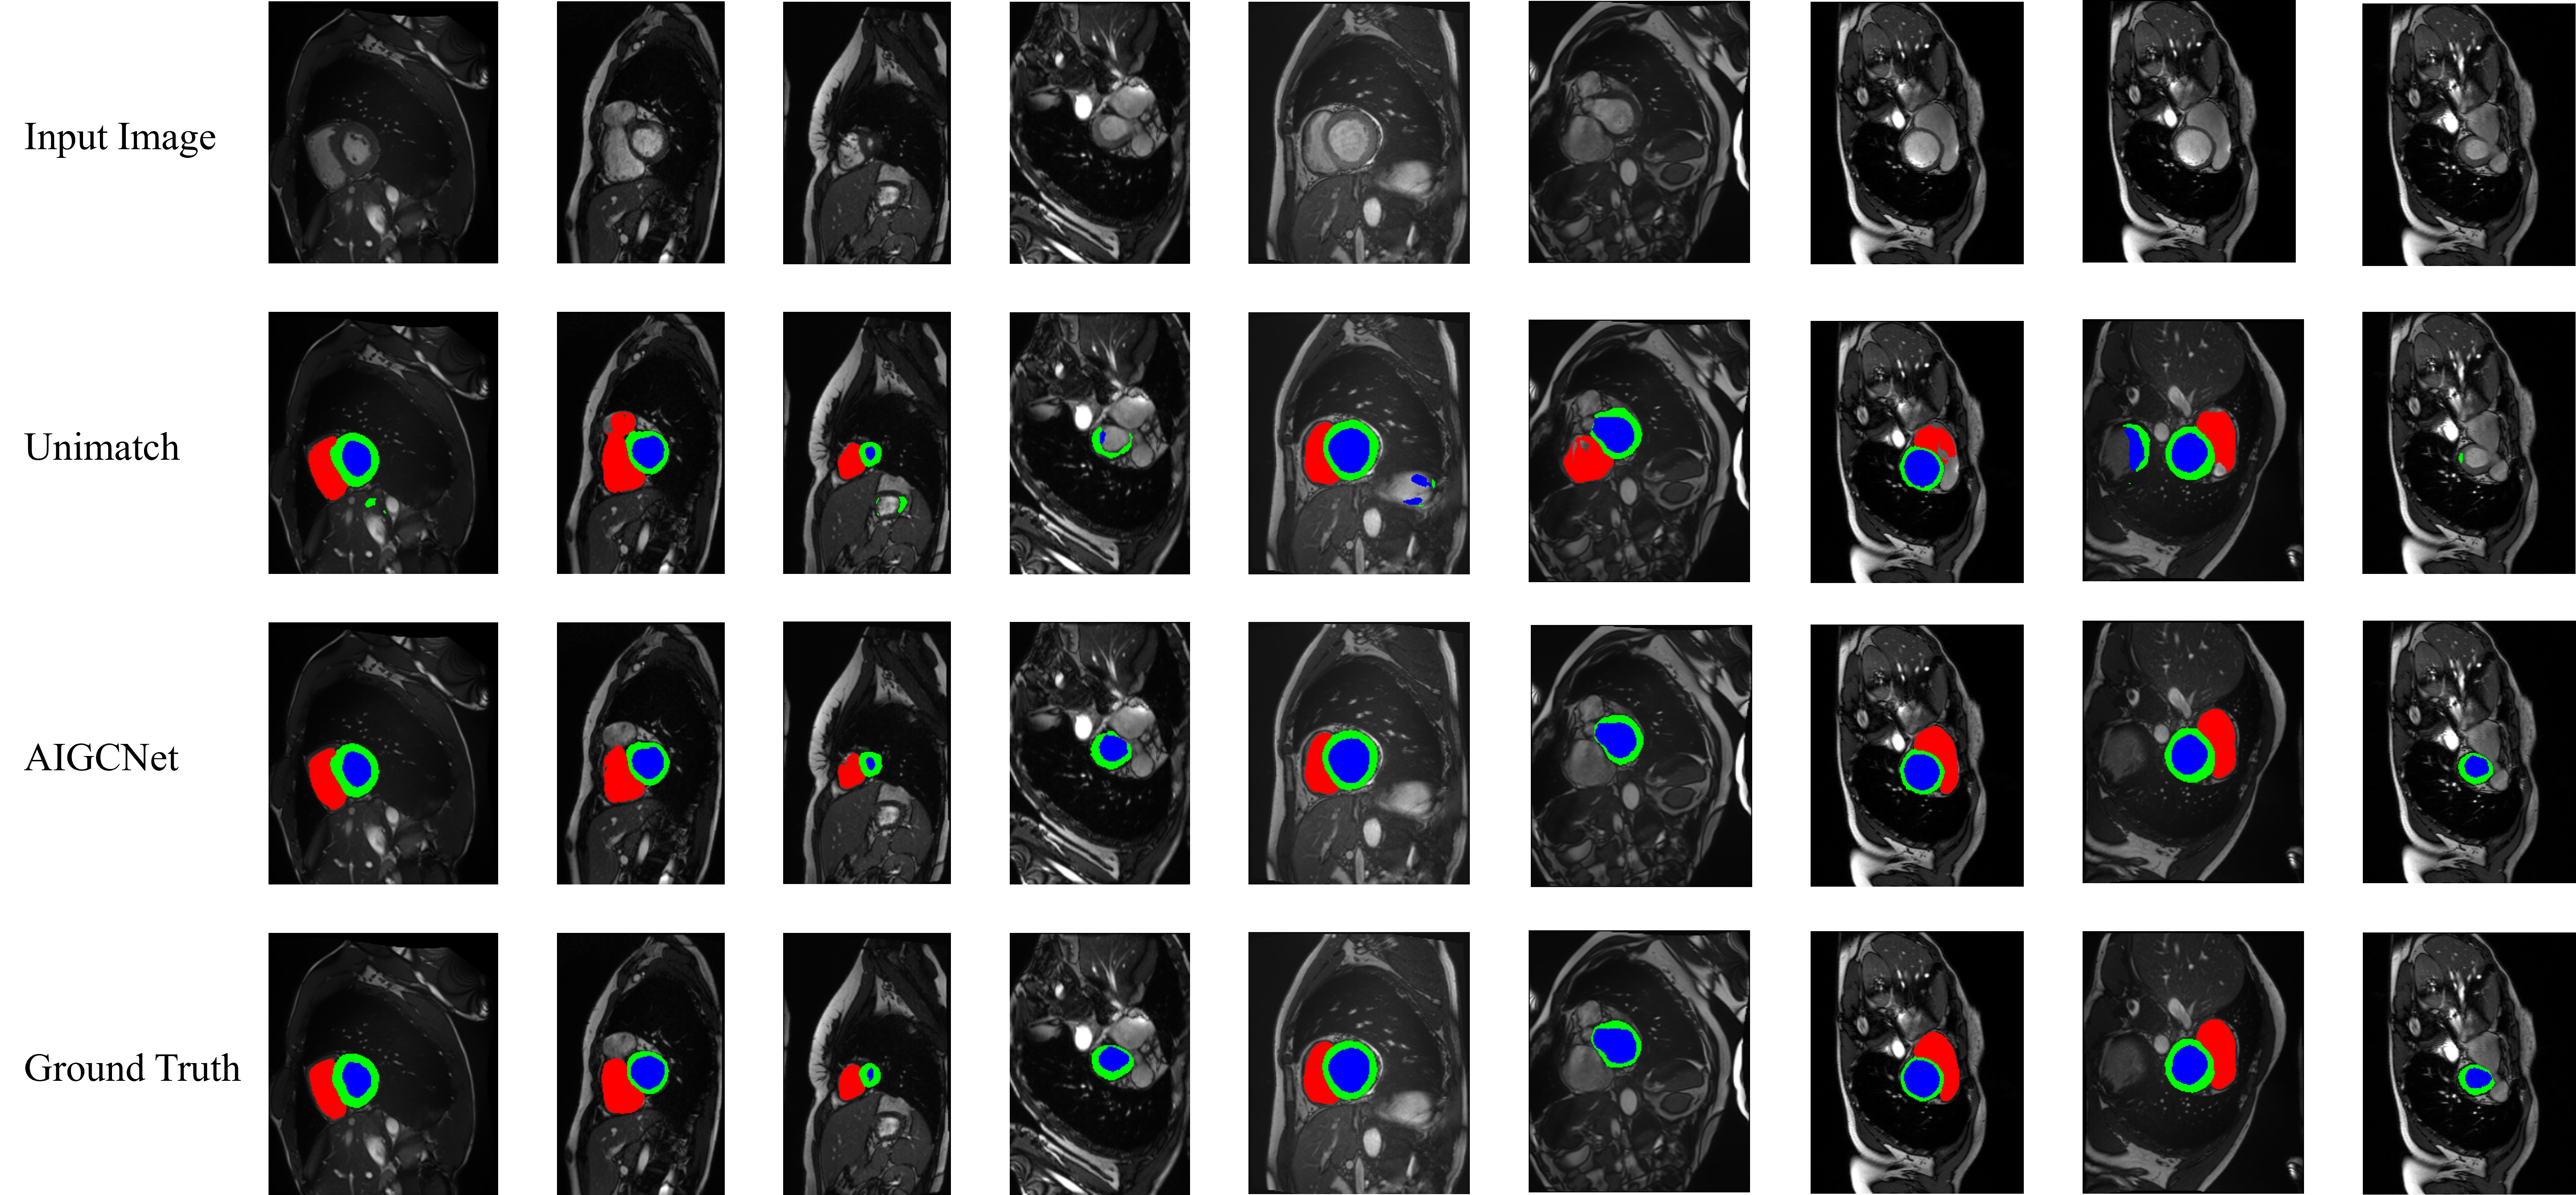

In this research, we evaluated our model’s performance on the ACDC and ISIC-2017 within a semi-supervised learning framework for medical image segmentation. The ACDC dataset[4], consisting of 100 two-dimensional cine cardiac MR images from the University Hospital of Dijon, is divided into 70 scans for training, 10 for validation, and 20 for testing. It is unique in targeting multiclass segmentation of cardiac structures, contrasting with other datasets that focus on binary segmentation. Within the domain of semi-supervised medical image segmentation, the ACDC dataset is conventionally divided into distinct segments categorized as 1-case, 3-case, and 7-case. These categories correspond to the utilization of 1%, 5%, and 10% of the available labeled data, respectively.

4.2 Semi-supervised image segmentation in ACDC

In the ACDC dataset, we compared our experimental results with those of multiple models, consistently achieving superior results. In comparison to the previous state-of-the-art (SOTA), our method demonstrated improvements across four metrics: DICE, Jaccard, 95HD, and ASD.